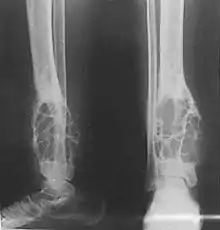

Adamantinoma (from the Greek word adamantinos, meaning "very hard"[1]) is a rare bone cancer, making up less than 1% of all bone cancers.[2] It almost always occurs in the bones of the lower leg[3] and involves both epithelial and osteofibrous tissue.[4]

Patients typically present with swelling with or without pain. The slow-growing tumor predominantly arises in long bones in a subcortical location (95% in the tibia or fibula).[3] Most commonly, patients are in their second or third decade, but adamantinoma can occur over a wide age range.

Histologically, islands of epithelial cells are found in a fibrous stroma. The tumor is typically well-demarcated, osteolytic and eccentric, with cystic zones resembling soap bubbles.[2]

Diagnosis is on plain radiography, or CT scan